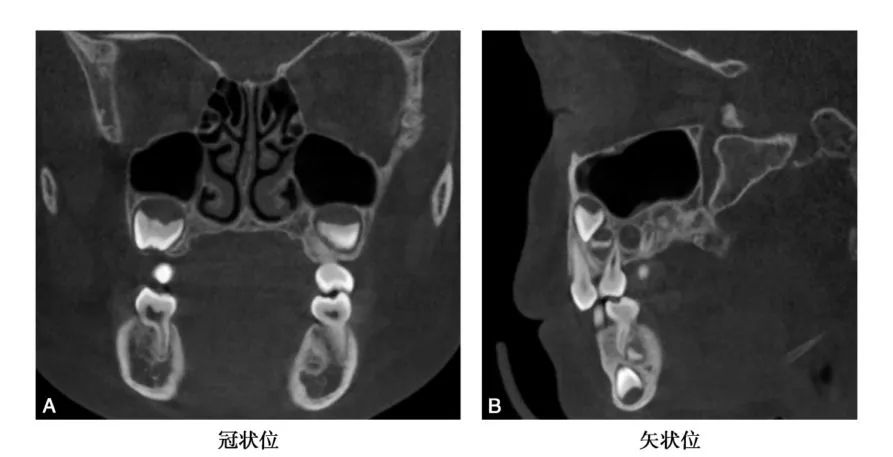

CBCT图像显示上颌窦是一个形状不规则,大小也不尽相同的腔,矢状位上是一由上、下、前、后壁构成的类似四方形或者梯形结构(图1-1-12)。冠状位上可见上颌窦上、下、内、外壁,形态多不规则(图1-1-13)。水平位可见前外、后外、内壁,中份多为类三角形,两端形态多不规则(图1-1-14)。上颌窦腔的容积为9. 5~20ml,平均为14. 75ml。不同人上颌窦形状和大小差别较大,同一个体双侧上颌窦形态基本对称(图1-1-15),但也存在同一个体两侧上颌窦形状和大小有差异(图1-1-16)。

CBCT矢状位示上颌窦形状不规则,类似四方形或者梯形结构

CBCT冠状位可见上颌窦上、下、内、外壁,窦腔形态不规则

A、C.可见窦腔形态不规则; B.窦腔形态类似三角形